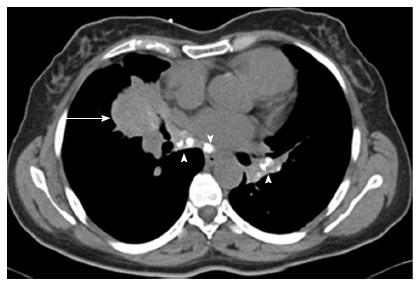

Inflammatory pseudotumor (IPT) has always been considered a diagnostic challenge. Its rarity and resemblance to other more common pathological entities imposes that neither clinical nor radiological characteristics can lead to a definitive diagnosis. The surgical excision of the lesion is the ultimate approach for accurate diagnosis and cure. Moreover the true nature of IPT, its origin as a neoplastic entity or an over-reactive inflammatory reaction to an unknown trigger, has been a long debated matter. Surgery remains the treatment of choice. IPT is mostly an indolent disease with minimal morbidity and mortality. Local invasion and metastasis predict a poor prognosis. We hereby present a unique case of pulmonary IPT that was surgically excised, but recurred contralaterally, shortly thereafter. Despite no medical or surgical treatment for ten years, the lesion has remained stable in size, with neither symptoms nor extra-pulmonary manifestations.

炎性假瘤(IPT)一直被认为是一个诊断难题。其罕见性以及与其他更常见病理实体的相似性使得临床和放射学特征都无法得出明确诊断。病变的手术切除是准确诊断和治愈的最终方法。此外,IPT的真正性质,即其作为肿瘤实体的起源或对未知触发因素的过度反应性炎症反应,一直是一个长期争论的问题。手术仍然是首选治疗方法。IPT大多是一种惰性疾病,发病率和死亡率极低。局部侵袭和转移预示着预后不良。我们在此报告一例独特的肺部IPT病例,该病例经手术切除,但此后不久在对侧复发。尽管十年未进行药物或手术治疗,病变大小一直保持稳定,既无症状也无肺外表现。